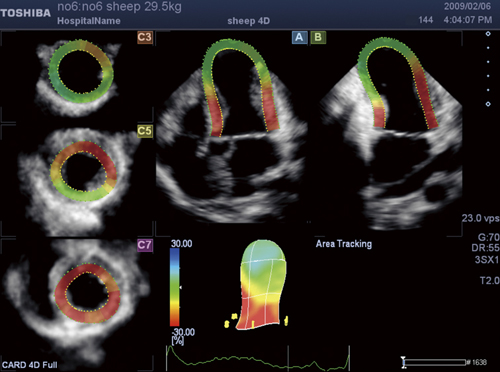

3d Wall Motion Tracking技術の特長と最新動向 東芝メディカルシステムズ株式会社 Innavi Suite

Artida の最新壁運動解析技術 東芝メディカルシステムズ株式会社 Innavi Suite